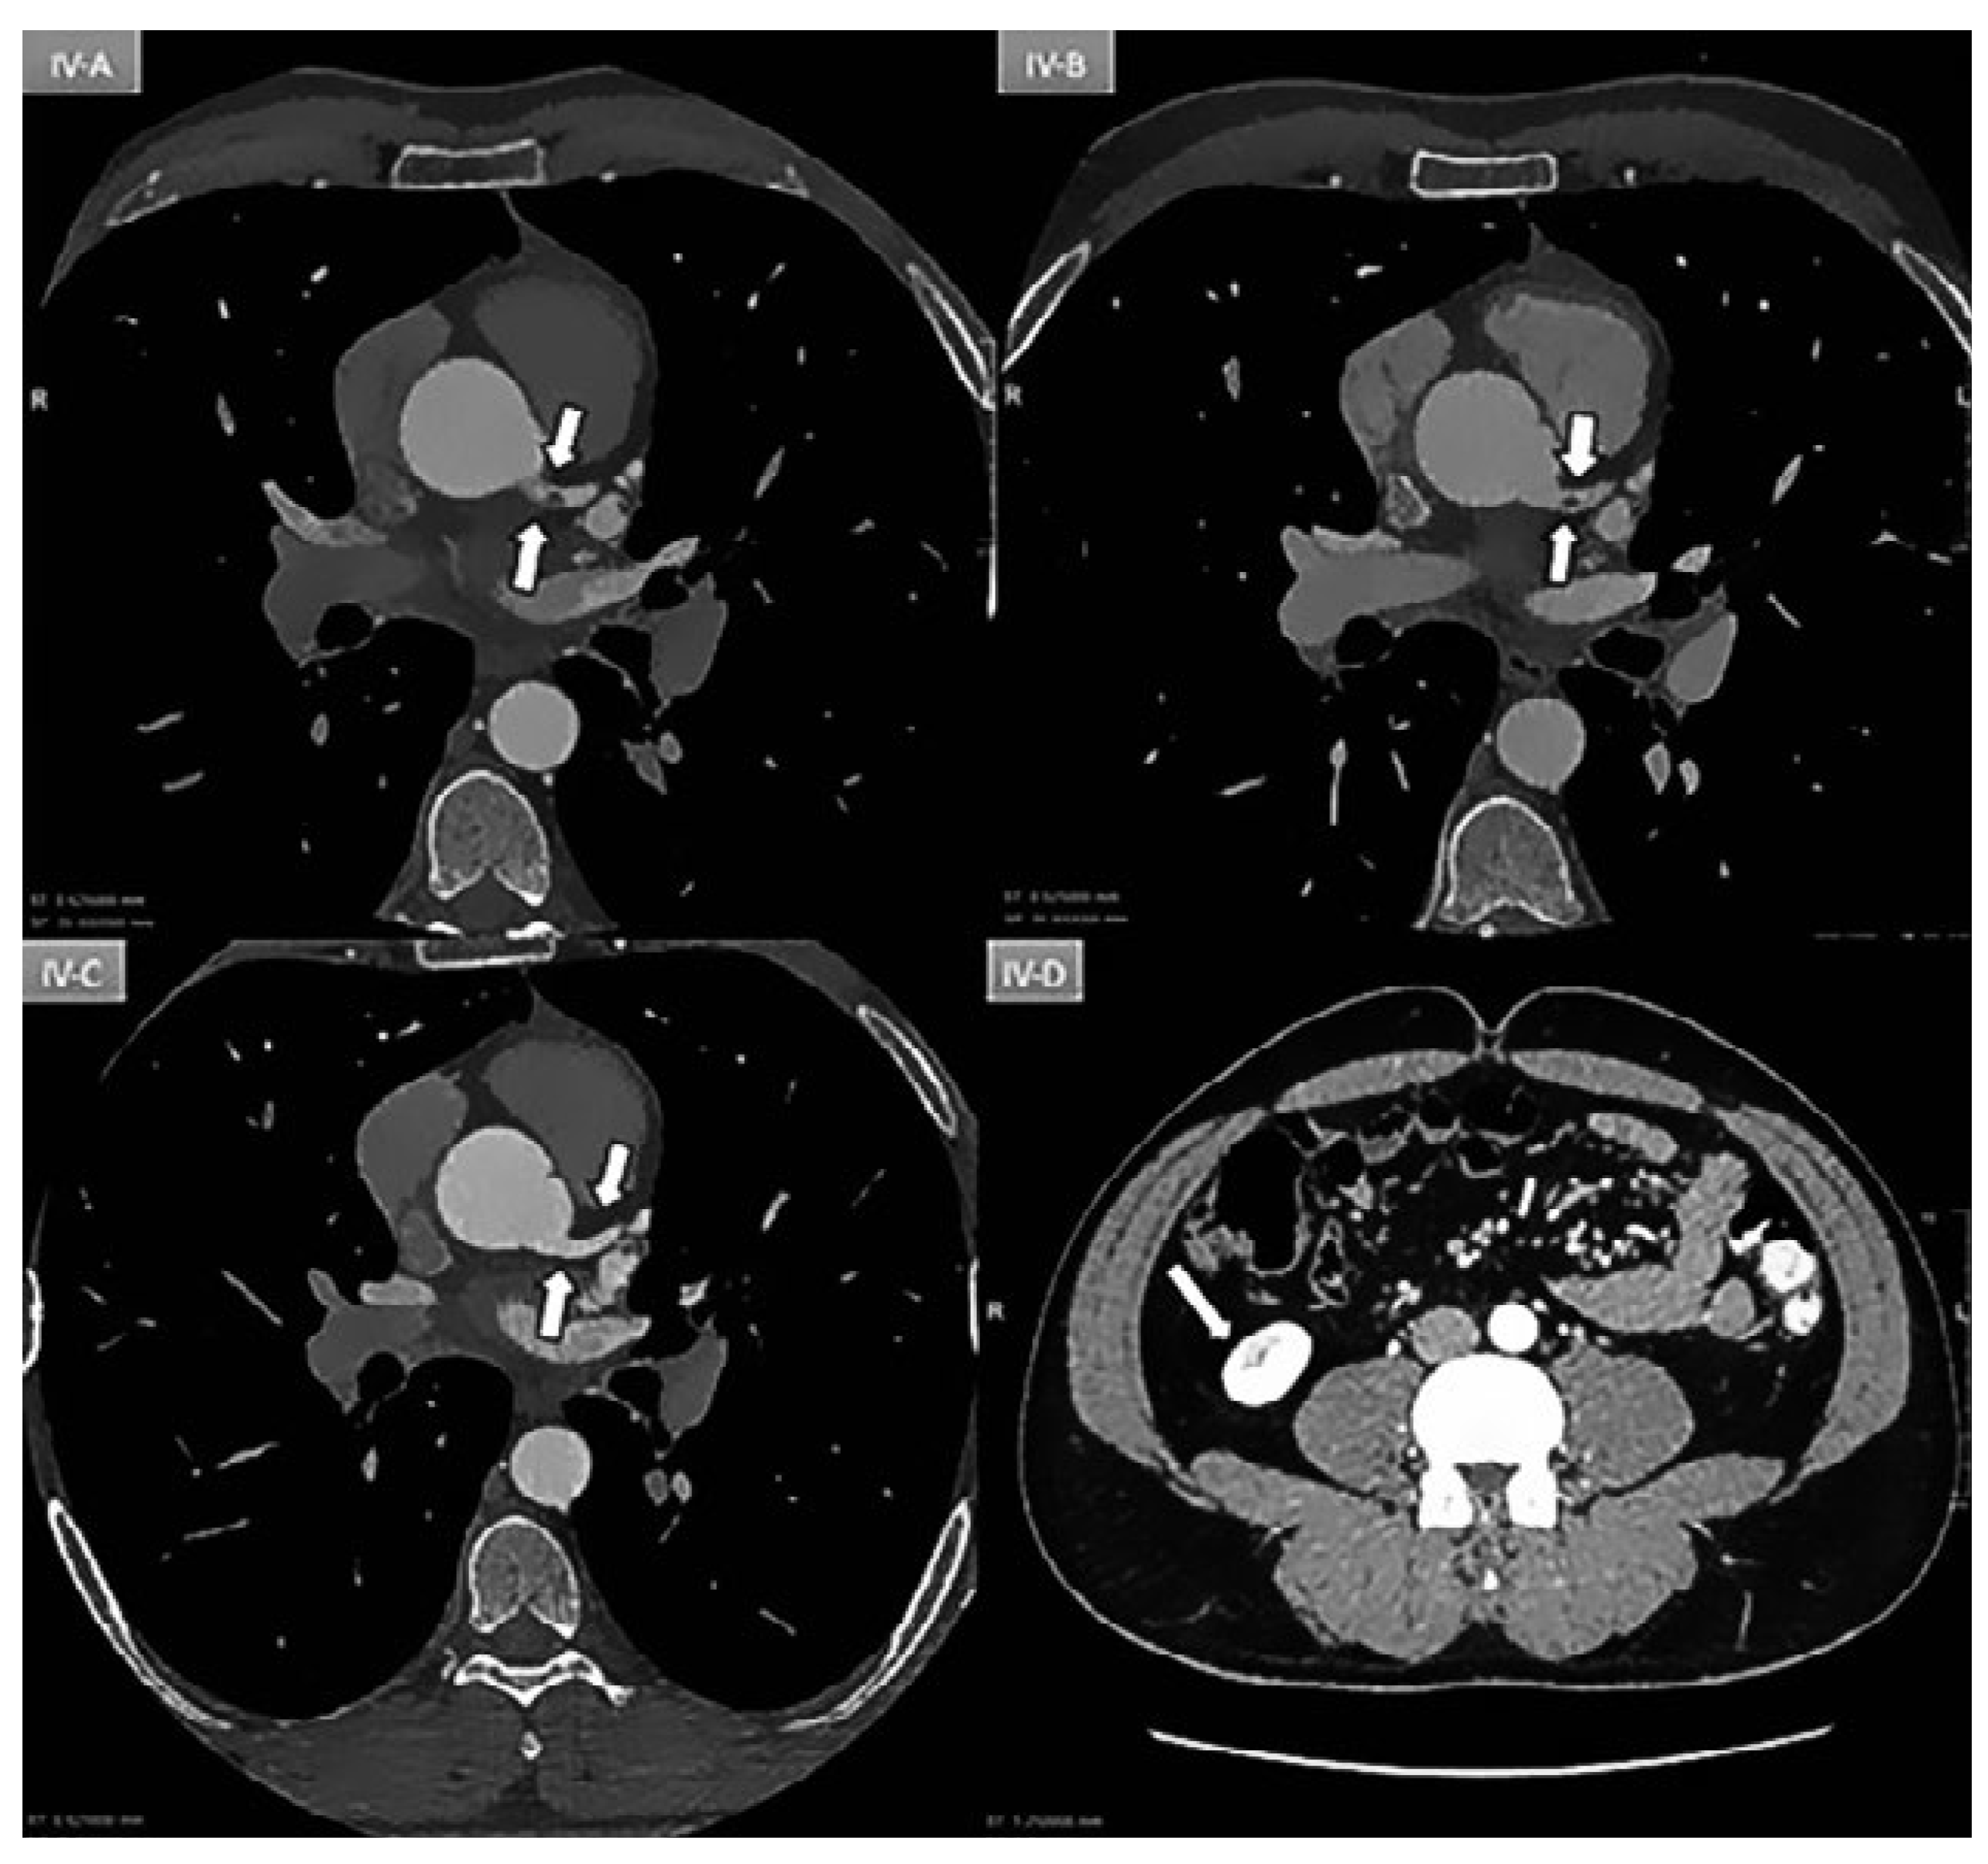

Figure 4.

A: Day 1: Coronary ECG-gating CT scan showing an intracoronary mass (arrow) partially occluding (70%) the lumen of the left main coronary artery. B: Day 3: Persistence of mass. C: Day 5: Patent vessel without any mass (arrow). D: Day-5: New triangular infarction of the lower pole of the right kidney consistent with peripheral embolisation.